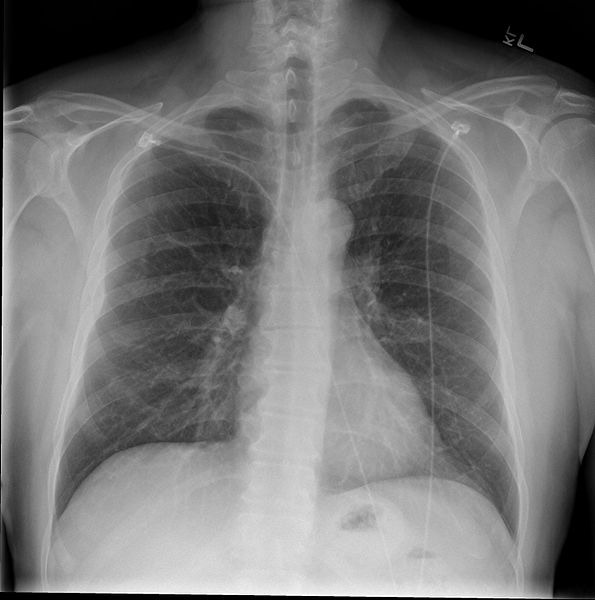

據The Verge報道,一家名為Oxipit的公司在一份聲明中說,一種可以在沒有放射科醫生監督的情況下讀取胸部X光片的人工智能工具上周在歐盟獲得了監管許可--這是完全自主的醫療成像人工智能首次在歐盟獲得批準。這是人工智能的一個重要里程碑,可能會引起爭議,因為放射科醫生在過去幾年里一直在抵制將其工作的一部分完全自動化的努力。

這款名為ChestLink的工具可以掃描胸部X光片,并自動發送它認為完全健康、沒有異常的病人報告。任何被該工具標記為有潛在問題的圖像都會被發送給放射科醫生進行審查。Oxipit公司在信息資料中說,初級保健中的大多數X射線沒有任何問題,因此對這些掃描進行自動化處理可以減少放射科醫生的工作量。

Oxipit在一份聲明中說,ChestLink在多個地點的試點項目中沒有出現“臨床相關”的錯誤。該公司說,當它被引入一個新環境時,首先應該對現有的成像程序進行審計。然后,該工具應該在監督下使用一段時間,然后再開始自主工作。